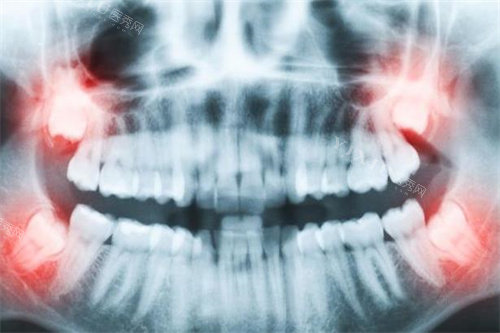

种植牙价格因种植体品牌、材质及手术复杂度呈现显著差异。爱齿口腔2026年单颗种植牙价格范围如下:

(三)种植配套项目

复杂病例需额外支付辅助手术费用:

骨增量手术:植骨粉(0.5g)2500元起,自体骨移植单部位3600元起,上颌窦提升术(简单型)5600元起。

智能化服务:3D种植导板制作1600元起,口扫建模与AI方案设计成为标配,提升手术精细度。